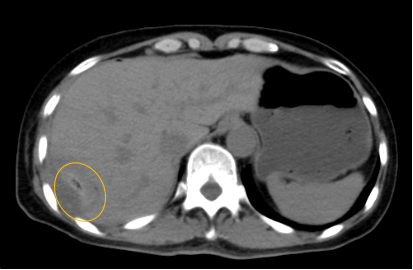

入院后,影像診療中心立即給李女士完善了CT和MR檢查,發(fā)現(xiàn)病變位于肝包膜下,臨近膈肌,消融治療過(guò)程中有并發(fā)損傷膈肌的可能,難度較大,但是采用精準(zhǔn)影像定位是可以完成的。陳寶瑩主任立即與腫瘤三病區(qū)劉金鵬主任聯(lián)系,并與影像微創(chuàng)治療小組進(jìn)行MDT討論:患者為卵巢癌肝右葉包膜下單發(fā)轉(zhuǎn)移瘤,最長(zhǎng)徑不超過(guò)3cm,患者對(duì)局部治療的主觀愿望強(qiáng)烈,符合消融治療專家共識(shí),遂制定了影像引導(dǎo)下局部消融治療聯(lián)合全身治療的綜合治療方案。

針對(duì)這個(gè)特殊部位的腫瘤,要想消融完全,那么膈肌損傷的風(fēng)險(xiǎn)就很高,陳寶瑩主任帶領(lǐng)影像微創(chuàng)亞專業(yè)組成員仔細(xì)閱讀CT圖像,設(shè)計(jì)進(jìn)針路徑,結(jié)合MR圖像確定腫瘤活性范圍,制定了周密而詳盡的消融計(jì)劃。臘月二十九,即住院第二天影像微創(chuàng)治療小組圓滿為患者完成了腫瘤微波消融治療,觀察24小時(shí)后出院回家過(guò)年。術(shù)后48小時(shí)隨訪患者無(wú)明顯不適,術(shù)后7天隨訪,患者肝功、血常規(guī)等各項(xiàng)指標(biāo)均恢復(fù)正常。